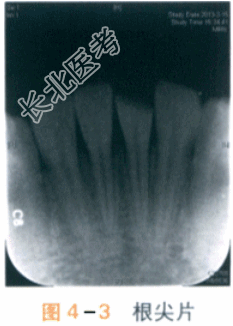

X线摄片显示:左下中切牙和右下中切牙牙根根周膜完整,未见明显根折线(见图4-3)。